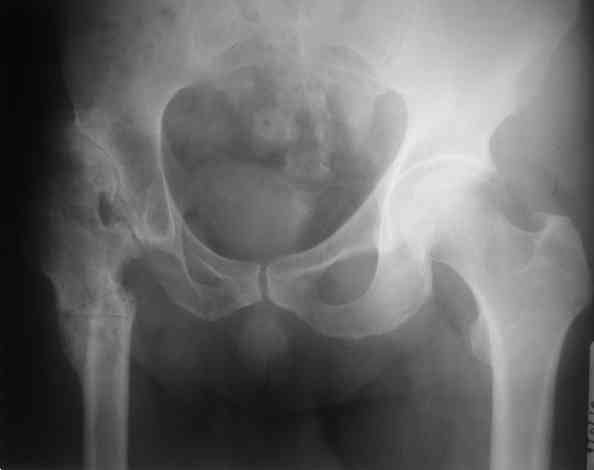

Уважаемый Андрей, ситуация не простая, нет обзорной Р-графии таза, поэтому сложно провести правильное планирование операции. Тем не менее, при планировании операции вертлужный компонент я бы установил в анатомическое положение. В отношении ножки - может быть два решения. Мое предпочтение - (операция типа Paavilaanen'a) поперечная остеотомия бедра на уровне чуть выше деформации, установка ножки Вагнера, скорее всего 190 мм, хотя возможно удастся обойтись и конической ножкой, это зависит от необходимой компенсации длины ноги. Продольная остеотомия б/вертела с последующей фиксацией к диафизу бедра с натяжением мышц. Есть и другой вариант - укорачивающая остеотомия в зоне деформации бедра с установкой ножки со стороны шейки. Мы делали и то и другое, первый вариант проще. В этой операции есть масса нюансов и нужно иметь опыт операций при дисплазии ТБС.

Уважаемые коллеги, без Р-граммы таза нельзя рекомендовать что-н.конкретно, представьте себе, что второй сустав находится в анатомическом положении,тогда позиция шейки протеза на оперируемой стороне будет примерно на уровне малого вертела, и тогда вам придется так укоротить б/вертел, что вы можете остаться без него.... Это очень не простые операции и нельзя без оценки всего таза что-н.советовать, во всяком случае мне так кажется

Уважаемый Андрей! Действительно сложно спланировать операцию без обзорного снимка таза, а так же рентгенограмы бедра в аксиальной проекции. По поводу реконструкции бедренной кости могу предложить следующие варианты опробированные на практике (если есть необходимость пришлю Р-граммы).